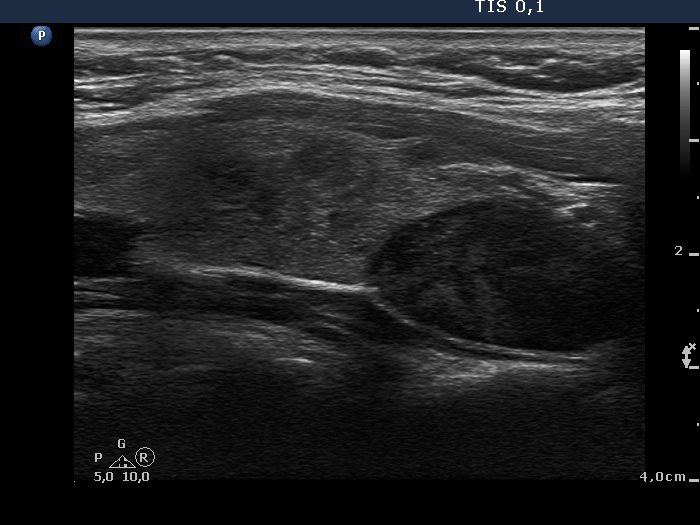

Parathyroid lesions - case 907 (ultrasonographic picture 5)

Lower part of the right lobe, another longitudinal scan.